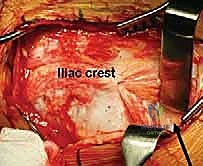

The Surgical Approach and Deep Dissection

We standardly employ the longitudinal anterior Smith-Petersen approach, which provides unparalleled direct access to the anterior pelvis. While a transverse "bikini" (ilioinguinal) incision offers a superior cosmetic result, it can severely restrict access to the deep anterior ischium, particularly in muscular or obese patients. The skin incision begins slightly proximal and lateral to the ASIS, extending distally along the interval between the tensor fasciae latae (TFL) and the sartorius.

During the superficial dissection, meticulous identification and protection of the lateral femoral cutaneous nerve (LFCN) are paramount. The fascia over the TFL is incised, and the interval between the TFL and the sartorius/rectus femoris is developed. The ASIS is often managed via a thin wafer osteotomy, leaving the sartorius and inguinal ligament attached, which facilitates later repair and prevents avulsion. Deep dissection involves elevating the iliacus muscle subperiosteally from the inner table of the ilium, exposing the pelvic brim, the quadrilateral plate, and extending posteriorly toward the greater sciatic notch.

Simultaneously, the outer table of the ilium is exposed by elevating the abductor musculature (gluteus medius and minimus) just enough to visualize the supra-acetabular region and the capsule. The rectus femoris origin at the AIIS is identified; the direct head is typically preserved, while the reflected head may be released to expose the superior joint capsule. Blunt retractors (such as a Hohmann or a specialized Ganz retractor) are carefully placed over the pelvic brim and into the obturator foramen to protect the neurovascular bundle during the subsequent osteotomies.